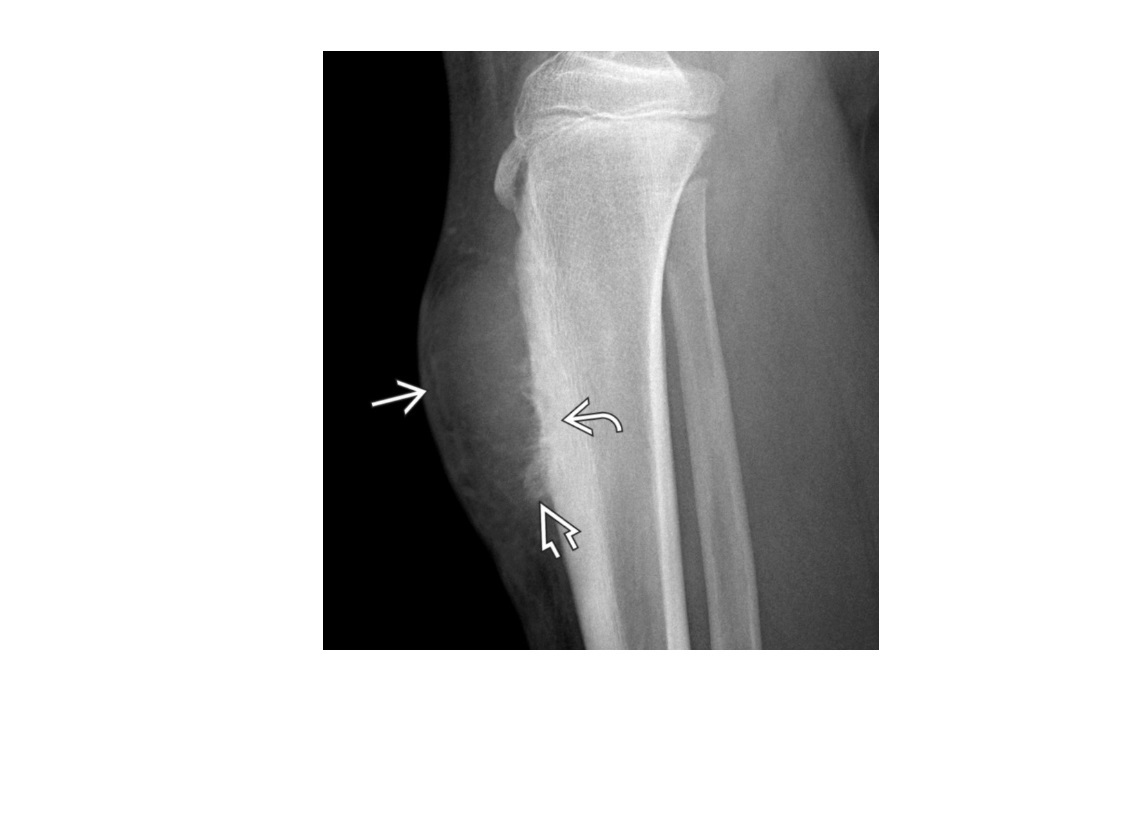

Segond fracture

Lateral tibial plateau

Associated with ACL tear (75%) and internal rotation

MR SL = Medial Reverse Lateral Segond

Reverse Segond fracture

Medial tibial plateau

Associated with PCL tear with external rotation. Associated with medial meniscus injury.

Arcuate sign

Avulsion of the proximal fibula

Associated with PCL tear